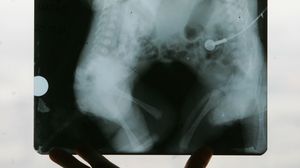

Cele doua micute, venite pe lume prematur, cantaresc sub 3 kg si au fost transferate la Spitalul Marie Curie din Bucuresti. Dupa primele investigatii, medicii sunt rezervati, spunand ca sansele de supravietuire sunt minime: micutele impart sternul, toracele, o parte din abdomen si o bucatica din ficat, insa ce e mai grav e ca au inima comuna, de fapt sunt doua inimi, care au vase de sange comune.

Lina si Gherghina, inainte de a fi despartite